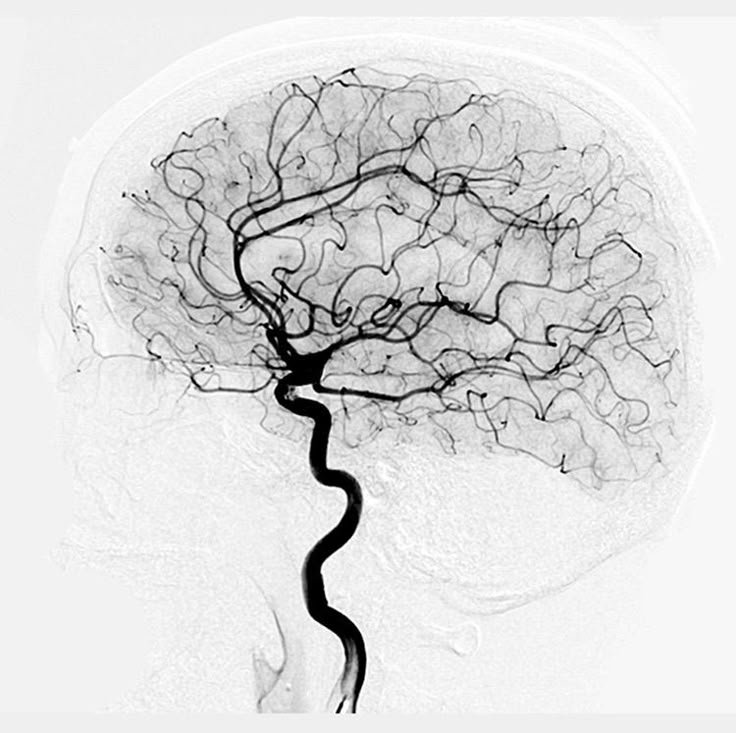

우리가 자주 느끼는 감정은 우리의 사고방식과 삶의 구조를 닮아 있습니다. 마치 나뭇가지처럼, 그 감정은 삶의 여러 장면 속으로 뻗어나갑니다.